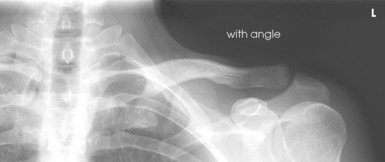

Structures shown: The joint space between the humeral head and the glenoid cavity (scapulohumeral joint) is shown (Figs. 5-19 and 5-20).

Structures shown: The scapulohumeral joint (Fig. 5-22) is seen.

Fig. 5-22 A, AP oblique projection: Grashey method, with shoulder showing normal scapulohumeral joint space. B, AP oblique projection: Apple method, with weighted abduction showing loss of articular cartilage (arrow).